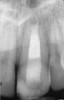

Fig 2. MTA placed in the apical third.

Figure 2

Fig 3. Postoperative radiograph.

Figure 3

Clinical procedure: If apical bone loss is present (Figure 1) a collagen/gelatin sponge (eg, Gelfoam®, Pfizer Inc., www.pfizer.com) can be placed apically so that the MTA can be delivered to the desired working length. (Any other surgical resorbable sponge would also work, such as OraPlug® [Salvin Dental Specialties, www.salvin.com], Surgifoam® [Midwest Dental, www.mwdental.com], or Surgispon® [Aegis Lifesciences, www.surgispon.com]). This is done by taking a small piece (2 mm x 2 mm) of the resorbable sponge and pushing it down to and through the root apex with an endodontic file. Once this is done, MTA is packed down the canal with a custom-fitted cone. The clinician can use a rubber stopper on the gutta-percha cone to know the exact length of MTA placed in the apical third (Figure 2). Once the apical third is sealed with 3 mm to 5 mm of MTA, the remaining coronal canal space can be back-filled using a warm gutta-percha technique (Figure 3).